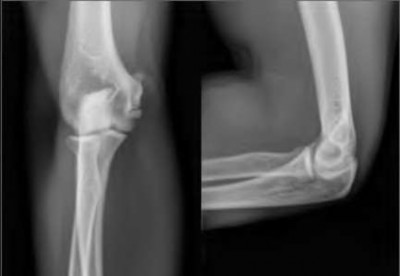

A 20-year-old park ranger trips and falls onto his right wrist with the wrist in extension and pronation. The local urgent care orders both radiographs and a CT, which you review and determine to be normal. The patient complains of ulnar-sided wrist pain. On exam, his tenderness is localized to the fovea. Ulnar deviation also causes him pain. There is no snapping sensation with wrist supination, flexion, and ulnar deviation. He otherwise has 5/5 strength to his first dorsal interosseous muscle with 4mm static two-point discrimination on the ulnar side of the 4th digit. Which of the following injuries is most likely responsible for his symptoms and exam?